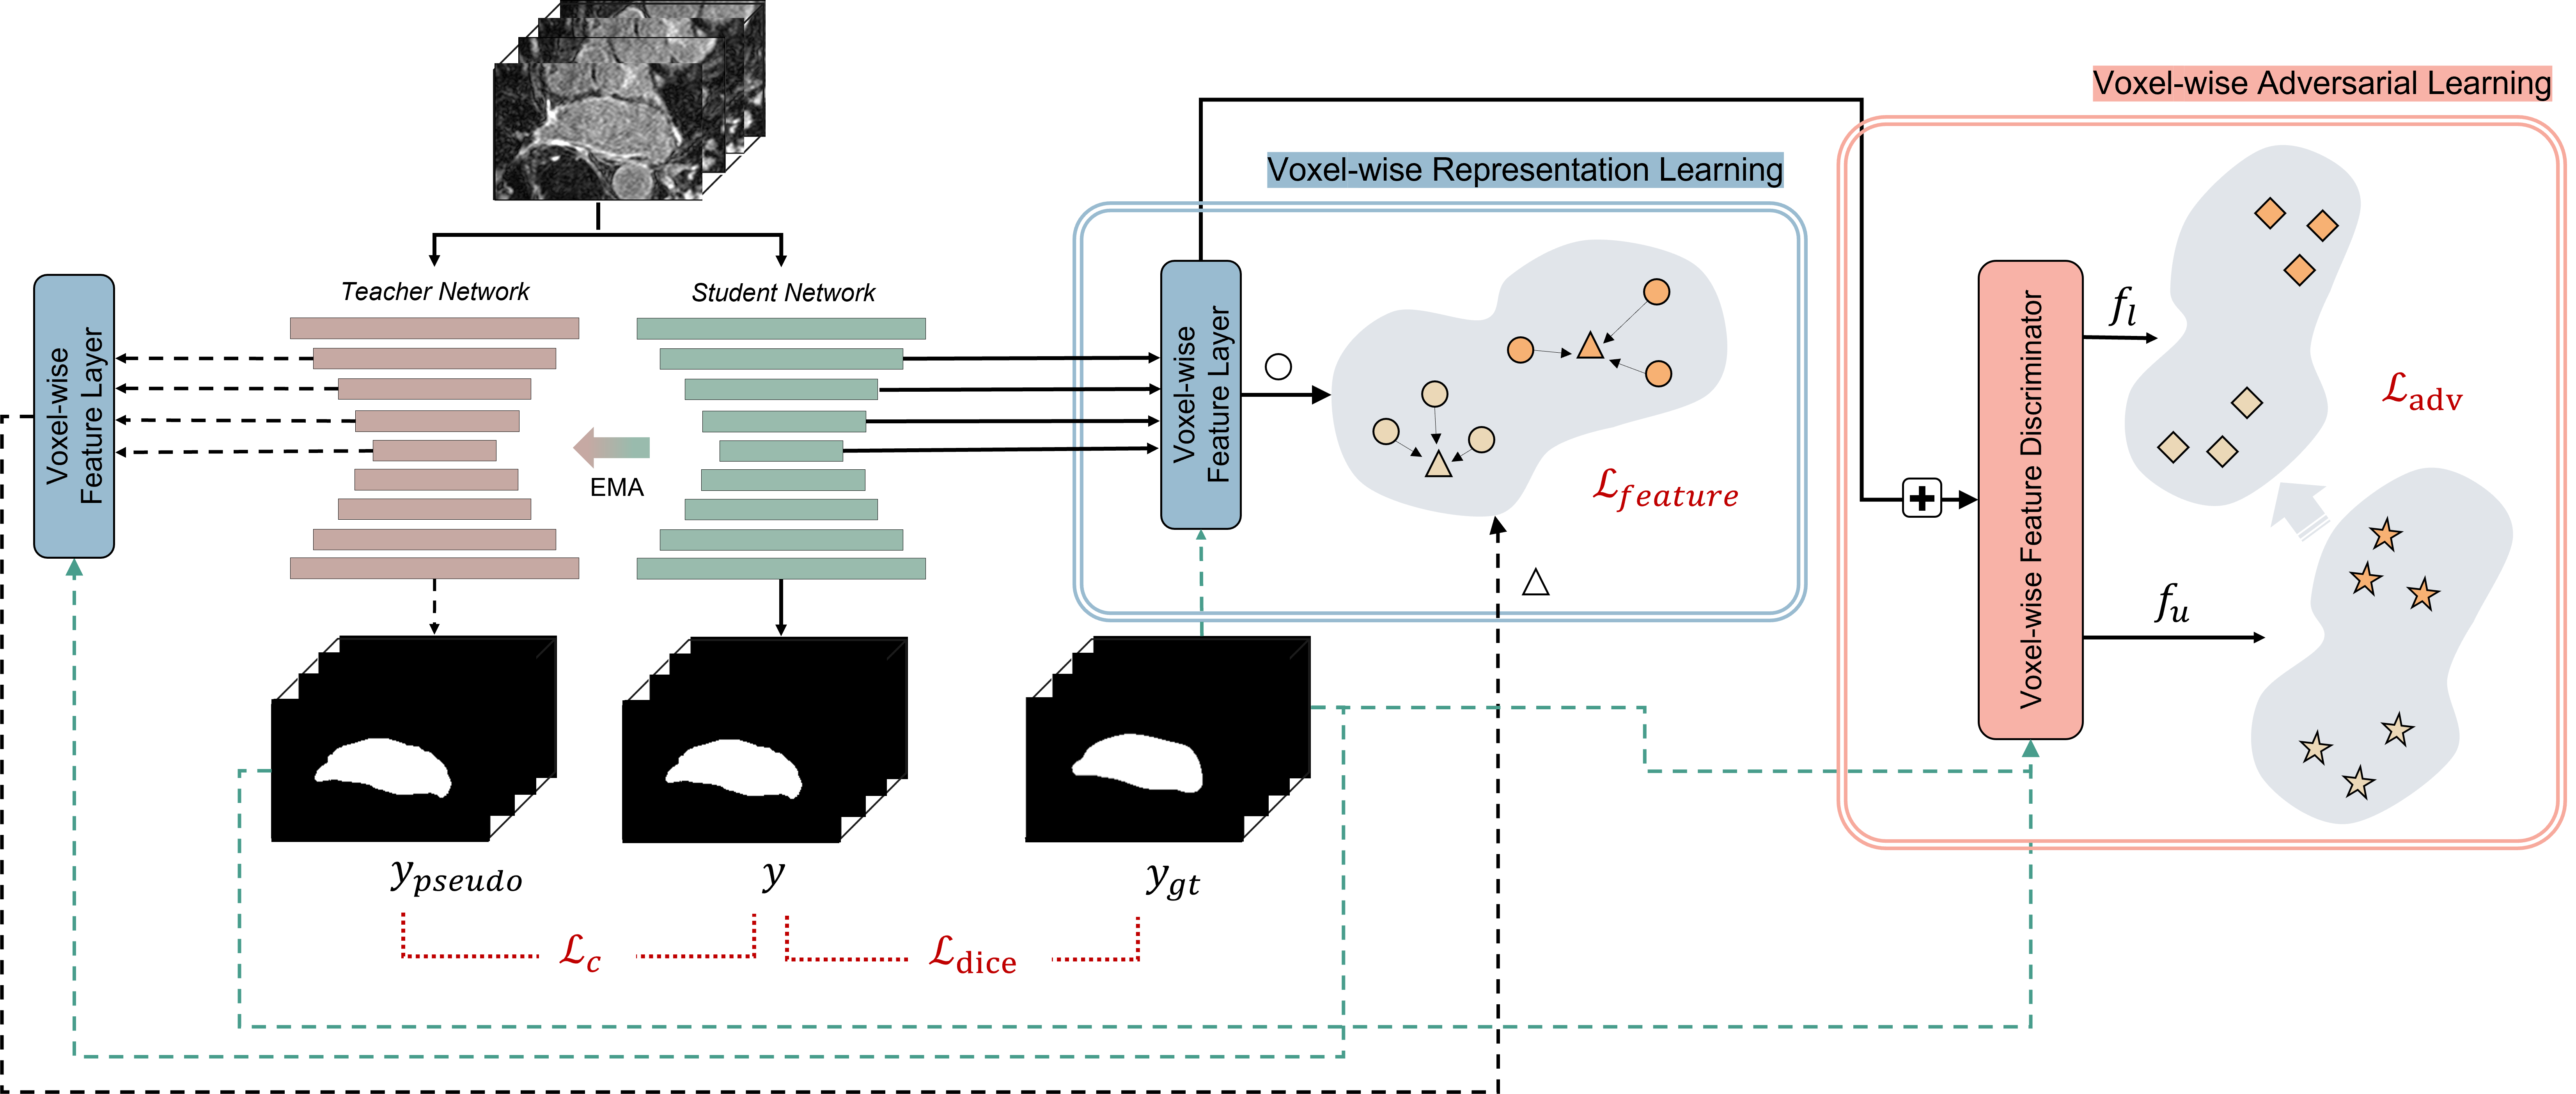

In this paper, we propose a novel adversarial learning-based method to incorporate unlabeled data to improve the network performance. We propose a context-aware semi-supervised segmentation method for efficiently learning the distributions of labeled and unlabeled datasets. To resolve the aforementioned problems of recent studies, we considered voxel-wise features from multiple hidden layers, which include both the local and global information of the data, as an input to our voxel-wise feature discriminator to embed distributions of unlabeled datasets. As illustrated in Fig. 1b, the job of this discriminator is to determine if a voxel-wise feature belongs to labeled data or unlabeled data (real for labeled data and fake for unlabeled data). This voxel-wise feature discriminator assumes the form of a multitask discriminator that can learn distributions from different classes simultaneously, thereby allowing us to embed class-specific context-aware features in the embedding space. Furthermore, we propose an improved voxel-wise representation learning method (Fig. 1a) for labeled data. To effectively embed unlabeled data, we are required to implement well-distributed features from labeled data prior to adversarial learning. In our previous study [14], we presented an explicit representation learning method for a supervised segmentation task by defining voxel-level feature relations. We adjusted this previous method to embed feature representations from labeled data without information loss using a multiresolution context resizing technique. Moreover, we used the Bootstrap Your Own Latent (BYOL) approach [15], instead of SimSiam [16], for learning stability.

We aim to learn feature representation (i.e., local and global features) from both the labeled and unlabeled datasets. To achieve this, we propose a context-aware semi-supervised segmentation method that can be incorporated into a segmentation network (i.e., VNet [30]). The overall architecture of semi-supervised segmentation is illustrated in Fig. 2. There exists a backbone network (i.e., VNet [30]) that takes labeled and unlabeled data (i.e., CT scans) as the inputs. We assume a set of training sets containing labeled data and unlabeled data, where . We denote the labeled set as and unlabeled set as , where represents the 3D volume, and denotes the ground-truth label. The proposed architecture for semi-supervised learning consists of two parts: voxel-wise representation learning (the blue box in Fig. 2) and voxel-wise adversarial learning (the red box in Fig. 2). Features from the hidden layers of the backbone network pass through each part to learn feature representations from and . The voxel-wise adversarial learning method takes voxel-wise features from and , after which it learns class-specific data distributions. The voxel-wise representation learning method uses voxel-wise features from and improves current embeddings by defining feature relations from the same class. In Section III-A and III-B, we describe the details of these methods. In Section III-C, we explain the overall training process of our proposed method.

III-A Voxel-wise Adversarial Learning

To leverage a large amount of unlabeled data, the network must be able to learn feature representations using only CT images. Previous consistency-based methods [10, 11] have applied a consistency loss function and trained the network for consistent prediction with perturbed or transformed outputs. The consistency loss is computed between and for labeled and unlabeled data. However, this loss is computed in the last layer (i.e., decision space), which embeds only the local features of data. Moreover, it penalizes voxel-wise consistency ignoring class-specific information. It is also problem in [13] that embedded shape-aware global features are only limited to a single class.

To resolve this problem, we propose a novel voxel-wise feature discriminator for embedding class-specific features of both labeled and unlabeled data. As presented in Fig. 3a, our voxel-wise feature discriminator takes a set of multiresolution features, , as an input, where denotes an encoder of the backbone, and denotes features from the hidden layer. These features from multiple hidden layers pass through the convolution layer to adjust the channel size, and each feature is upsampled to the same spatial size. Such features from multiple hidden layers are fused into one by adding an operation and a convolution layer. Thereafter, voxel-level features (-d vector) from this fused feature, , pass through a voxel-level feature discriminator, which consists of two multilayer perceptron networks (MLPs) and prediction layer (i.e., linear branch). The number of prediction layers corresponds to the number of class (in case of LA dataset, there exist two classes; foreground and background). The voxel-level features from different classes pass through different prediction layers. To specify the class of each voxel-level feature, we use ground-truth label for labeled data and pseudo-labels for unlabeled data, which can be computed using the following equation:

This different prediction branches enable multiple simultaneous adversarial classification tasks. We define features from labeled data as real and those from unlabeled data as fake so that the encoder of the segmentation network (generator) can generate voxel-level features of unlabeled data with a distribution similar to that of voxel-level features of labeled data. This forces the distributions of class-specific voxel-level features from both labeled and unlabeled features to be close. In this manner, the segmentation network can learn class-specific context-aware features more effectively. The encoder can embed both local and global features using a multiresolution context-fusion technique. In representing the voxel-wise feature discriminator, we can define our proposed adversarial loss function as follows:

III-B Voxel-wise Representation Learning

In Section III-A, we propose a new voxel-wise feature discriminator for learning the feature representations of unlabeled data via learning based on the feature distribution of labeled data. In this setting, the most important task is the modeling of the distribution of features from labeled data beforehand. Accurate modeling of the labeled data distribution is essential for effective adversarial learning. In other words, the model is unlikely to learn effectively from adversarial learning if the distribution of labeled data is incorrect. In contrast, the model is likely to learn effectively if distribution is recovered from labeled data. Thus, our model can learn rich feature representations from both labeled and unlabeled data.

In our previous work [14], we proposed a voxel-level Siamese representation learning method for medical image segmentation tasks. By defining voxel-wise feature relations in the representation space, the model learned feature representations that were effective in the segmentation task. We used the stop-gradient technique and Siamese network from SimSiam [16] to learn voxel-wise feature relations. We also proposed multiresolution feature aggregation method for embedding both local and global features. However, our previous study had two limitations: (1) learning stability and (2) information loss.

In this study, we propose an improved voxel-wise representation learning method for embedding features from labeled data. Inspired by previous studies [15, 31], we used the learning technique from BYOL [15], instead of SimSiam [16], for the first problem(i.e., learning stability). Using EMA from BYOL enabled the model to produce a more stable prediction target [31] than the stop-gradient technique from SimSiam [16]. As presented in Fig. 3b, there are teacher and student models; however, the teacher model uses the slow moving average of the student parameter, instead of learning for its own parameter (i.e., EMA). We update the weights of the teacher as , where represents the decay parameter, and indicates the weights of the student. Furthermore, for the second problem (i.e., information loss), we propose multiresolution context resizing method. The information loss occurs during the downsampling of mask data to match the class location for each voxel-wise feature. Thus, instead of downsampling the mask data, we upsampled the multiresolution features from the encoder, . Figure 3b illustrates the upsampling and convolution stage that can reduce information loss.

As explained in Section III-A, our voxel-wise feature layer (Fig. 2 and Fig. 3b) uses multiresolution features from the encoder of the backbone as an input. These features pass through the upsampling and convolution stages, and voxel-wise features, , are selected for each class; here, refers to the voxel-wise feature from class (class-specific feature selection). These sampled voxel-wise features pass through the projection and prediction layers. The projection layer from the teacher network outputs , and the projection and prediction layers from the student network output , where denotes the prediction layer. Based on a previous research [15], we used the mean square error between normalized and as the feature loss function. The feature loss function for updating the student network can be defined as follows:

III-C Training Details

Our backbone network is based on VNet [30]. We first demonstrate a basic VNet [30] segmentation training scheme for a labeled dataset. Two VNets [30] are displayed in Fig. 2: the teacher and student networks. These two networks take the 3D volume, , as an input, and they output prediction masks, and respectively. Based on [10, 13], we used the dice loss [32] to maximize the overlap between the ground truth and prediction to train the student network. We used the labeled dataset (i.e., ) to compute the dice loss, which can be defined as

Following [7], we also added a consistency loss between the softmax predictions of the teacher and student networks for semi-supervised learning. The consistency loss between the outputs of the teacher and student networks can be summarized as follows:

The final loss function for training the student network (i.e., VNet [30]) is summarized as follows: